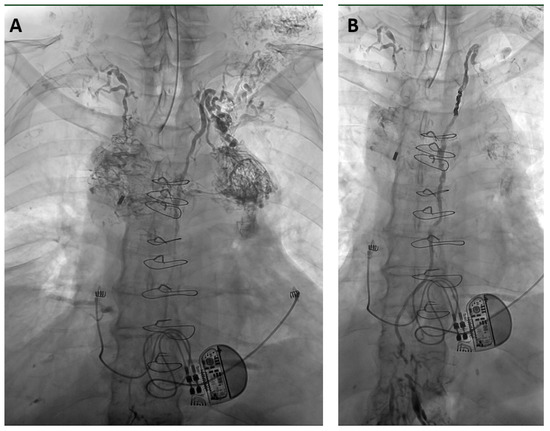

2.2. Interventional Technique

3.4. Clinical Success